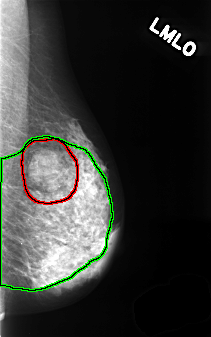

FILE: C_0366_1.LEFT_MLO.OVERLAY

TOTAL_ABNORMALITIES 2

ABNORMALITY 1

LESION_TYPE MASS SHAPE LOBULATED MARGINS OBSCURED

ASSESSMENT 4

SUBTLETY 5

PATHOLOGY BENIGN

TOTAL_OUTLINES 1

BOUNDARY

ABNORMALITY 2

LESION_TYPE CALCIFICATION TYPE PLEOMORPHIC DISTRIBUTION DIFFUSELY_SCATTERED

ASSESSMENT 3

SUBTLETY 3